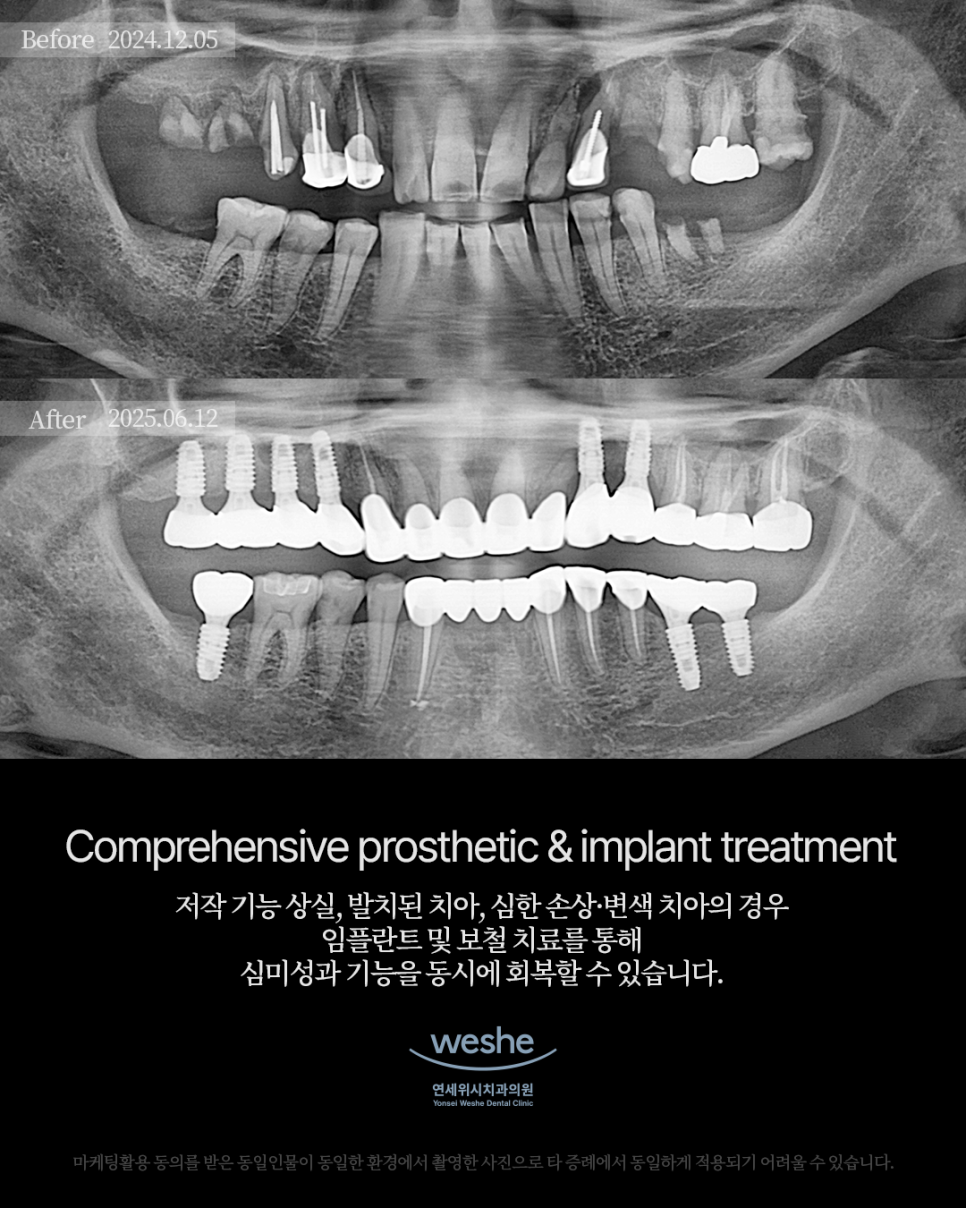

저작 기능 상실, 발치된 치아, 심한 손상과 변색 치아의 경우

임플란트 및 보철 치료를 통해

심미성과 기능성을 동시에 회복할 수 있습니다.

짧은 기간 안에 완성된 변화를

Before & After로 확인해보세요.